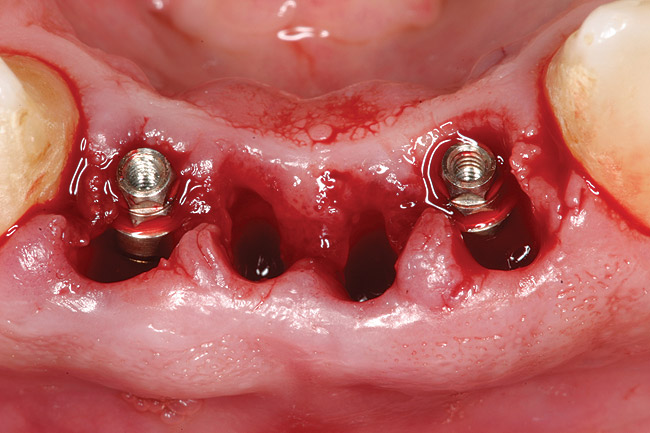

Preoperatively, 1 g of amoxicillin was administered. Using local anesthesia (lidocaine 1:100,000 epinephrine), extractions of teeth No. 23 to No. 26 were performed without raising a flap and with gentle luxation to preserve the remaining facial osseous plate. The sockets were curetted prior to implant placement. A vacuum-formed surgical guide, fabricated based on a diagnostic wax-up of the desired tooth positions for the subsequent fixed prosthesis, was used during implant placement. Osteotomies were performed at sites No. 23 and No. 26 and positioned toward the lingual aspects of the sockets (Figure 3A and Figure 3B). Two tapered implants (OsseoTite™ 313, BIOMET 3i™, Palm Beach Gardens, FL) measuring 3.25 mm x 13 mm were placed. Conical prosthetic abutments (3-mm height) were used to facilitate joining the two implants in a screw-retained fixed partial denture (Figure 4). A laboratory-processed acrylic-resin provisional restoration was altered to allow connection to the temporary cylinders. The provisional was placed into the vacuum-formed surgical guide that was now used to maintain the provisional in the correct 3-dimensional position (Figure 5) while being attached to the temporary cylinders with acrylic resin intraorally. Once a sufficient amount of acrylic resin was placed to secure the cylinders to the provisional, it was removed from the mouth and its contours were completed at the laboratory bench (Figure 6A). The two central incisor sockets were grafted with small-particle allograft material (Puros® Allograft, Zimmer Dental, Carlsbad, CA) to maintain gingival architecture beneath two ovate pontics (Figure 6B). The provisional restoration was inserted and the screws tightened to 20 Nt-cm of torque.

Figure 3a 3  Osteotomies prepared lingually.

Figure 3a

Figure 3  Placement of implants without flap elevation.

Figure 3

Figure 4  Tapered implants with conical transgingival abutments and temporary cylinders in place.

Figure 4